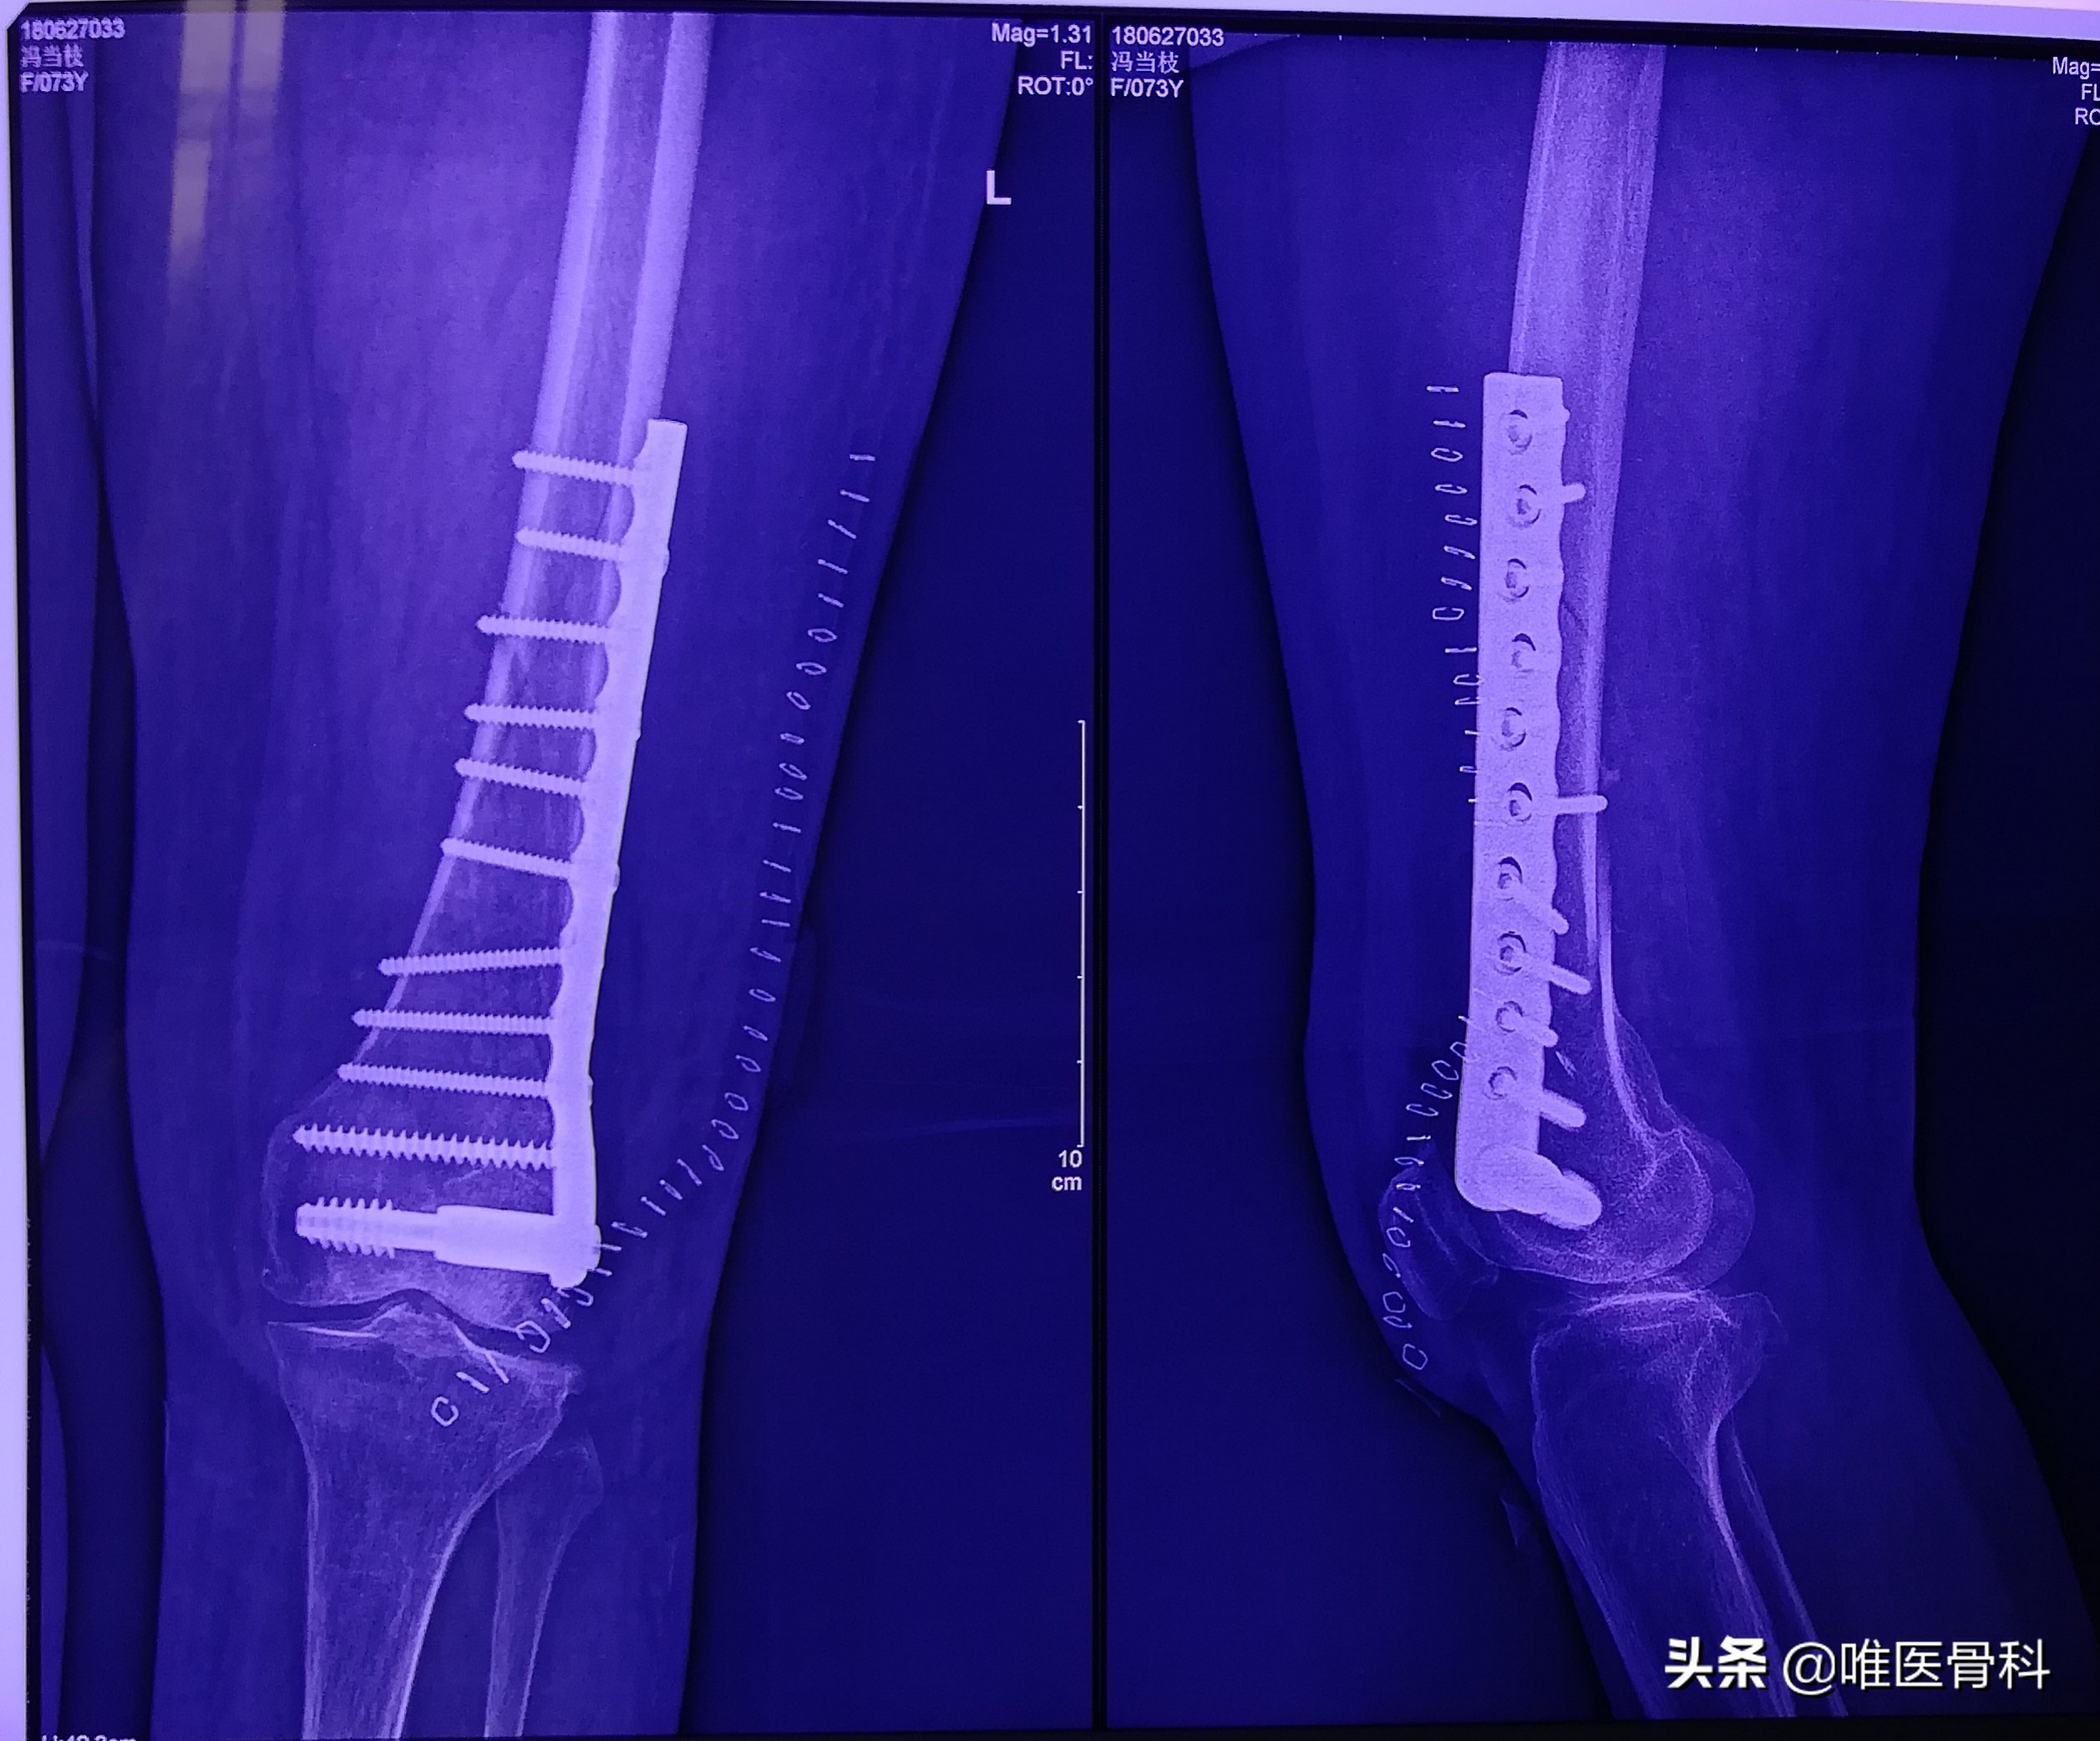

2.固定及原理

骨折复位后,因不稳定,容易发生再移位,加重周围软组织损伤和剧烈疼痛。开放骨折还会引起感染,因此要采用不同的方法将其固定在满意的位置,使其逐渐愈合。

常用的固定方法有:小夹板、石膏绷带、外固定支架、牵引制动固定等,这些固定方法称外固定。

如果通过手术切开用螺钉、钢针、钢丝、钢板、髓内针、及其组合等固定,则称内固定。

螺钉、钢针、钢丝单独或通过钢板、髓内钉将骨折缝合起来,起到保持复位的固定作用,经过一定时间,骨折愈合,恢复功能。

而且医生总是建议用组织相容性好、硬度接近生物力学的钛钉、钛板,既有利于复位固定,又有益于丰富骨痂形成。骨折固定原则是用最简单的方式,获得最牢固的固定。